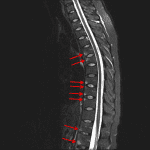

- T2/STIR signal hyperintensity in the anterosuperior and anteroinferior corners of the T5-T6, T8-T10, and T12-L2 vertebral bodies

- T2/STIR signal hyperintensity about the left T3-T4 costovertebral joint and to a lesser extent about the costovertebral joints bilaterally at T5-T6, on the right at T7-T8, and on the left at T9-T10

- Likely multilevel bridging anterior syndesmophytes

- Ankylosing spondylitis

Edema in the anterior aspects of the endplates about the T5-T6, T8-T9, T9-T10, T12-L1, and L1-L2 intervertebral discs, edema about multiple bilateral costovertebral joints most pronounced on the left at T3-T4, and likely multilevel bridging anterior syndesmophytes. These findings are most suggestive of an inflammatory spondyloarthropathy, particularly ankylosing spondylitis. Recommend rheumatology evaluation.

Given the increased vulnerability to fractures in patients with ankylosing spondylitis, dedicated CT imaging should be considered for further evaluation if there is a history of trauma.

No abnormal cord signal or significant mass effect on the thecal sac in the thoracic spine.